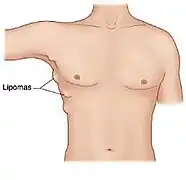

Lipoma

A lipoma is a benign tumor made of fat tissue.[1] They are generally soft to the touch, movable, and painless.[1] They usually occur just under the skin, but occasionally may be deeper.[1] Most are less than 5 cm (2.0 in) in size.[2] Common locations include upper back, shoulders, and abdomen.[4] It is possible to have several lipomas.[3]

Lipomas have a prevalence of roughly 2 out of every 100 people.[2] Lipomas typically occur in adults between 40 and 60 years of age.[1] Males are more often affected than females.[1] They are the most common noncancerous soft-tissue tumor.[5] The first use of the term "lipoma" to describe these tumors was in 1709.[6]